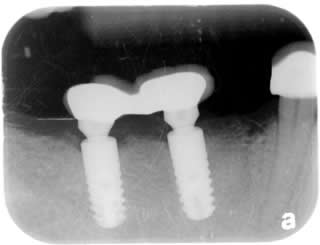

Implant Rescue:

Implants were placed a year ago outside of Canada by patient’s previous dentist.  Unfortunately the adjacent tooth was damaged during the surgery causing infection to the dental implant.

The chronic infection destroyed the bone causing a big void around the dental implant.  The patient received the implant rescue procedure at Liberty Square Dental Centre by Dr. Yeh.

The radiograph is taken 4 months after the implant rescue procedure showing great amount of bone formed around the implant.

At Liberty Square Dental Centre we are capable of treating a variety of implant problems.